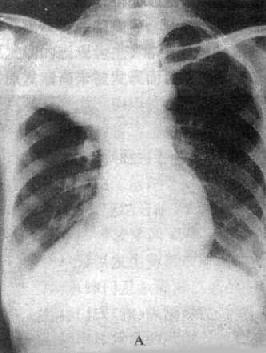

图3-1-24 右肺中心型肺癌伴肺门淋巴结转移

A.后前位 B.右侧位 C.侧位体层像

右肺门区可见圆形肿块影,边界清楚

体层摄影示肿块影边界不规则(→),

并见增大淋巴结向支气管突入